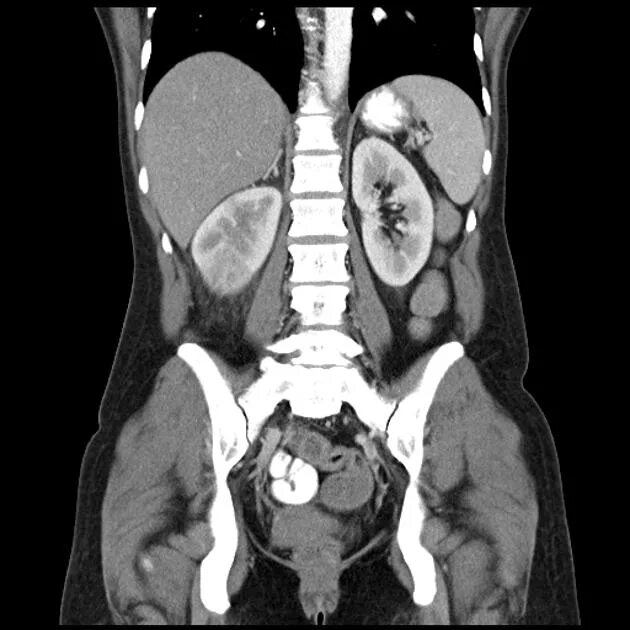

Пиелонефрит кт